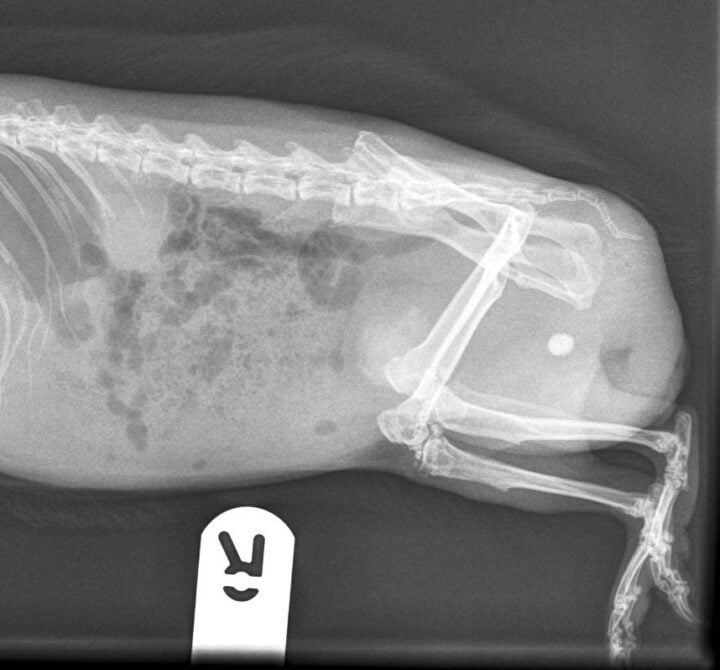

Common symptoms of urolithiasis in guinea pigs include stranguria, haematuria and signs of discomfort or pain when urinating, such as vocalisation. Diagnosis of urolithiasis in guinea pigs is similar to diagnosis in rabbits, using physical examination, urinalysis and imaging techniques, such as radiographs or ultrasound. Radiographs will often reveal the presence of stones (Figure 4), though small stones may be missed if they are not radiopaque. Ultrasound can be particularly useful for detecting smaller stones or those located in the kidneys or ureters.

Diagnosis is achieved through radiographs, ultrasound and urinalysis in the same way as rabbit and guinea pig patients. Radiographs will typically reveal the presence of radiopaque stones, while ultrasound can help identify smaller or less visible stones. Urinalysis may show the presence of crystals, bacteria or blood. Surgical cystocentesis to remove the stone is often the treatment of choice. Following removal of the stone, submitting the sample for culture and composition analysis may prove useful in treatment. Prevention of further urolithiasis formation involves dietary modification by transitioning the patient to an animal-protein-based diet and increasing water intake.